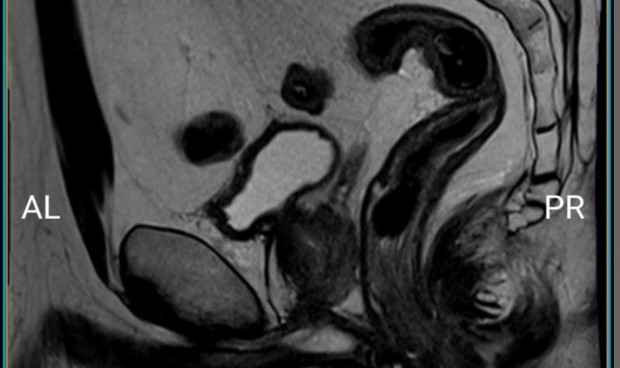

Entre las funcionalidades más destacables, se encuentran: La disponibilidad y acceso de los pacientes a su documentación administrativa y clínica, así como la visualización y descarga de las imágenes radiológicas. También, La visualización de las citas que tienen pendientes, con la hora y el centro sanitario al que tienen que acudir y la posibilidad de guardarla en el calendario del teléfono móvil.

Según Vicent Moncho, director de Sistemas y Tecnologías de la Información del DSD: “El principal beneficio es disponer en tu móvil de los resultados de las pruebas como las imágenes radiológicas” y añade: "La app permite a los pacientes tener un control sobre su proceso asistencial. Además, es muy sencilla de usar por su arquitectura y permite a los usuarios realizar gestiones sin visitar el mostrador administrativo ni perder tiempo en el teléfono". La aplicación de Mostrador Virtual MS es gratuita y está disponible tanto en 'Apple Store' para los usuarios de iPhone como en 'Play Store' para los de android.